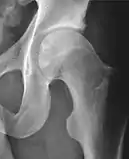

| Center-edge angle of Wiberg | ![]() |

The superior-lateral coverage of the femoral head. | |